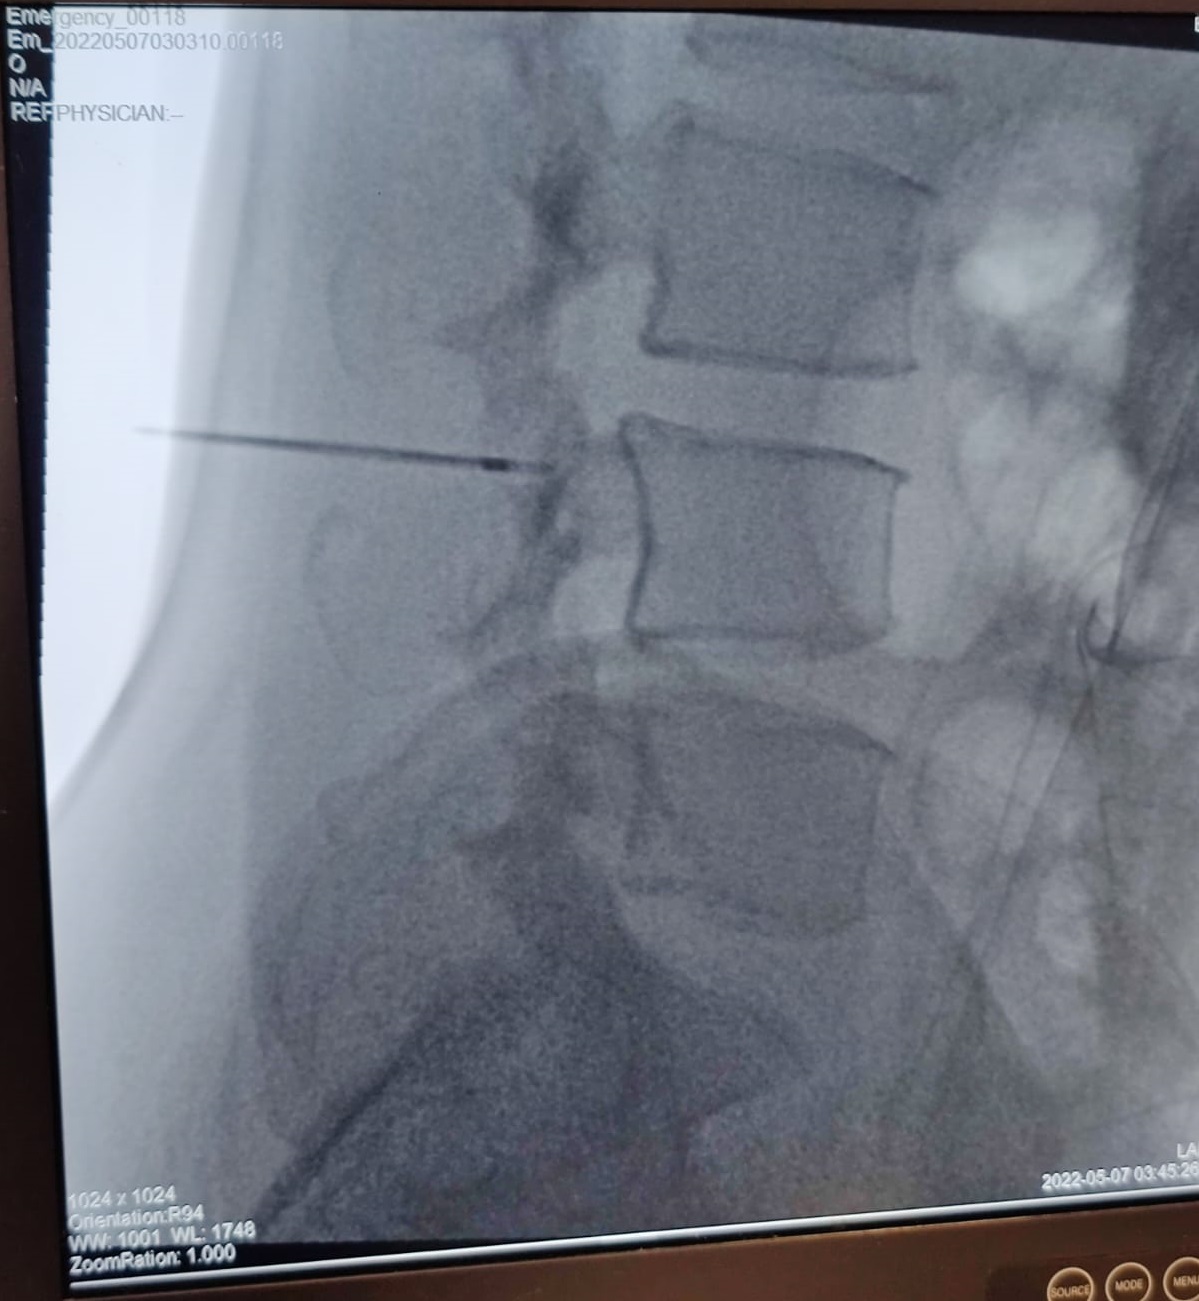

Facet joint injections:

This MIPSI intervention is targeted at injecting a very low dose of steroid into the facet joint space under the guidance of Fluoroscope machine. This brings about reduction in the inflammation of the joint reducing the pain and stiffness of the joint.